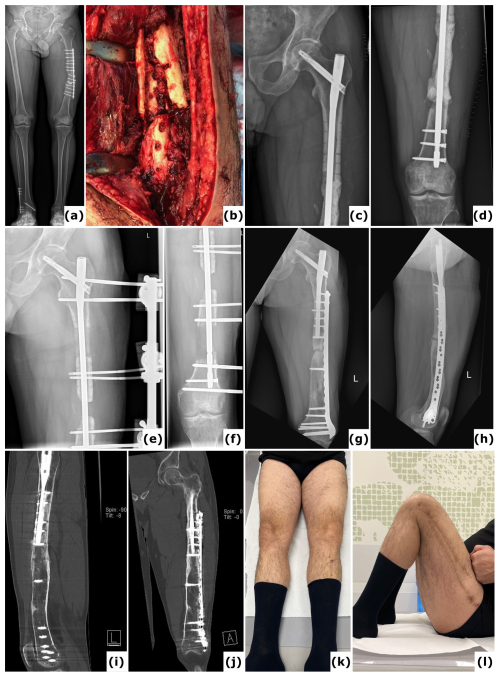

Figure 1A case of polymicrobial fracture-related infection (FRI) of the femur resulting from a gunshot injury is described. A 44-year-old polytrauma patient presented with multiple injuries, including a Gustilo-Anderson type III open femur fracture of the left lower limb. (a) The patient was transferred after initial stabilization, external fixation of the left femur, and several surgical wound debridements. (b) Anteroposterior radiograph of the left femur was taken following acute shortening, distal corticotomy, and lengthening. No cultures were collected during this surgery. (c–d) Computed tomography (CT) images of the left femur at 6 months show a persistent unhealed fracture site along with a distal distraction site that is not fully consolidated. Due to the presence of suggestive signs of FRI (local redness, swelling, and elevated serum inflammatory markers), local debridement of the fracture site was undertaken. Cultures grew Klebsiella pneumoniae and Enterococcus faecalis, for which the patient received systemic antibiotic therapy (6 weeks). (e) Clinical image of a classic ring fixator. (f–g) Lateral and anteroposterior radiographs after removal of the external fixator at 2 years demonstrate consolidation of the fracture and the distal distraction site. Because of continued pin site infections, local redness, and elevated serum inflammatory markers, the intramedullary canal was reamed and cultures were obtained, all of which were positive for Staphylococcus aureus. Again, the patient received systemic antibiotic therapy (6 weeks). (h) Clinical images of the lower limb 1 year after removal of the external fixator show significant scarring of the left thigh from the pin tracts. Knee flexion was limited to 10°. This case shows that long-term external fixation is not harmless and can be associated with several potential complications, such as joint contracture, scarring from the pin tracts, and severe chronic infections.

Figure 5Trifocal transport over a nail. A 44-year-old patient presented with a fracture-related infection of the femur following plate osteosynthesis. (a) A long-leg radiograph obtained 6 months after the initial procedure at another institution shows an unhealed fracture and failure of the osteosynthetic construct. (b) An intraoperative clinical image displays the comminuted (avascular) fracture site. Cultures identified Staphylococcus epidermidis. (c–d) Anteroposterior radiographs of the left femur taken postoperatively reveal a large segmental defect, treated with an intramedullary nail and a PMMA spacer. (e–f) Anteroposterior radiographs document progression of the bone transport. (g–h) One-year anteroposterior and lateral radiographs demonstrate removal of the external fixator and revision to a nail/plate construct; cultures from this surgical intervention were negative. (i–j) Computed tomography (CT) images at 2 years confirm consolidation at all sites. (k–l) Clinical images at 2 years illustrate a full range of motion in both lower extremities.